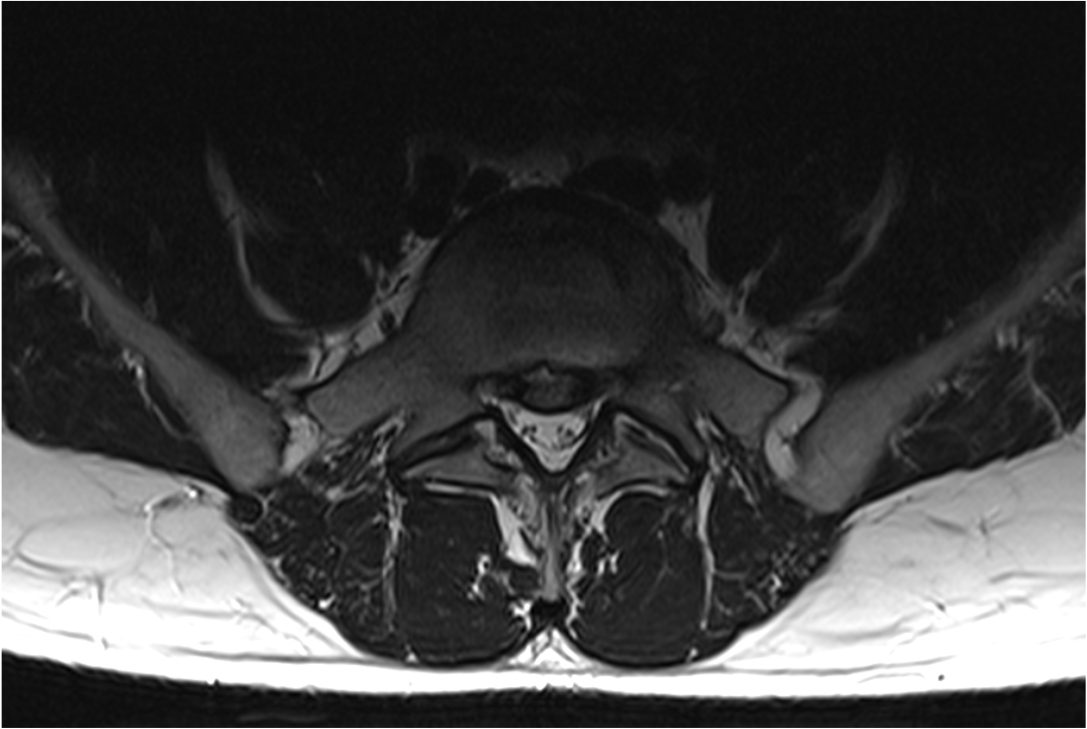

Die MRT-Bilder zeigen einen 78-jährigen Patienten mit Schwäche- und Taubheitsgefühlen in den Beinen, schon nach 20 Meter Gehstrecke.

Das erste Bild zeigt eine Einengung des Spinalkanals in 3 Höhen, das Zweite Bild zeigt den selben Patienten 6 Monate nach seiner OP.

Hier sieht man eine deutlich Entlastung der Nervenfasern. Im Gegensatz zum ersten Bild sind die Fasern nicht mehr gequetscht und zeigen um die Engstellen keine spiralförmige Aufwertung mehr.